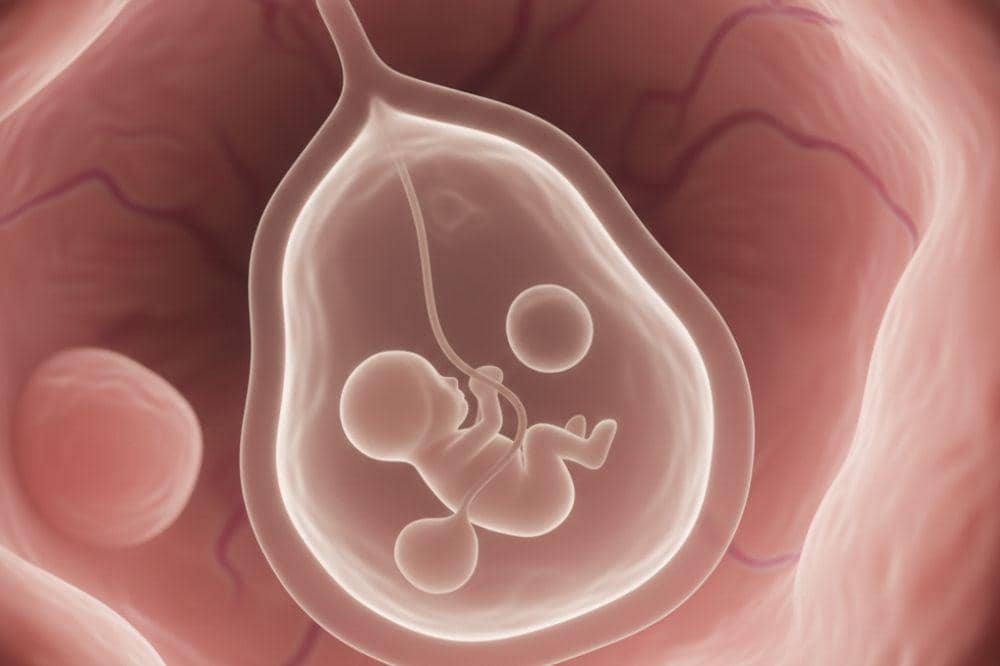

Kantung kehamilan atau gestational sac merupakan struktur pertama yang terbentuk di dalam rahim setelah terjadinya pembuahan. Bentuknya berupa kantung yang berisi embrio serta cairan ketuban yang mengelilinginya.

Kantung kehamilan terdiri atas dua lapisan, yaitu lapisan dalam yang disebut amnion dan lapisan luar yang disebut korion. Lapisan amnion akan terisi cairan ketuban yang berfungsi melindungi janin dari benturan dan perubahan suhu, sekaligus membantu menunjang perkembangan fisiknya.

Kantung kehamilan biasanya mulai terlihat berisi janin yang masih berada pada tahap embrio pada usia kehamilan sekitar 5–7 minggu setelah hari pertama menstruasi terakhir. Pada periode ini, hasil pembuahan telah menempel dengan pada dinding rahim dan mulai berkembang di dalam kantung kehamilan.

Pada awal kehamilan, janin tidak langsung terlihat bersamaan dengan kantung kehamilan. Yang pertama tampak hanyalah kantung kehamilan, sedangkan janin baru bisa mulai terlihat secara bertahap seiring perkembangannya.

Seiring perkembangan, embrio mulai tampak di dalam kantung kehamilan. Pada usia 6 minggu, pola janin awal terlihat. Memasuki usia 7–8 minggu, mulai menunjukkan struktur yang lebih jelas.

Kantung kehamilan yang normal biasanya berbentuk bulat atau oval dengan tepi yang jelas. Saat diperiksa menggunakan USG, kantung ini tampak berwarna putih keabu-abuan. Seiring berjalannya kehamilan, kantung akan semakin membesar.

Sekitar usia kehamilan 6 minggu, janin tampak seperti garis atau oval kecil di dekat kantung kuning, dengan ukuran sekitar 1–2 milimeter. Apabila kantung terlihat tidak beraturan atau dindingnya kurang jelas, hal ini dapat menjadi pertanda adanya masalah, seperti kehamilan yang tidak berkembang secara optimal.